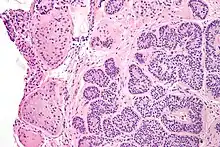

| Micrograph of a Sertoli cell nodule. H&E stain. | |

A Sertoli cell nodule is a benign proliferation of Sertoli cells that arises in association with cryptorchidism (undescended testis).[1] They are not composed of a clonal cell population, i.e. neoplastic; thus, technically, they should not be called an adenoma.[2]

Sertoli cell nodules are unencapsulated nodules that consist of:[2][3][4]

- cells arranged in well-formed tubules (that vaguely resemble immature Sertoli cells), with

- bland hyperchromatic oval/round nuclei that are stratified, and

- may contain eosinophilic (hyaline) blob in lumen (centre).